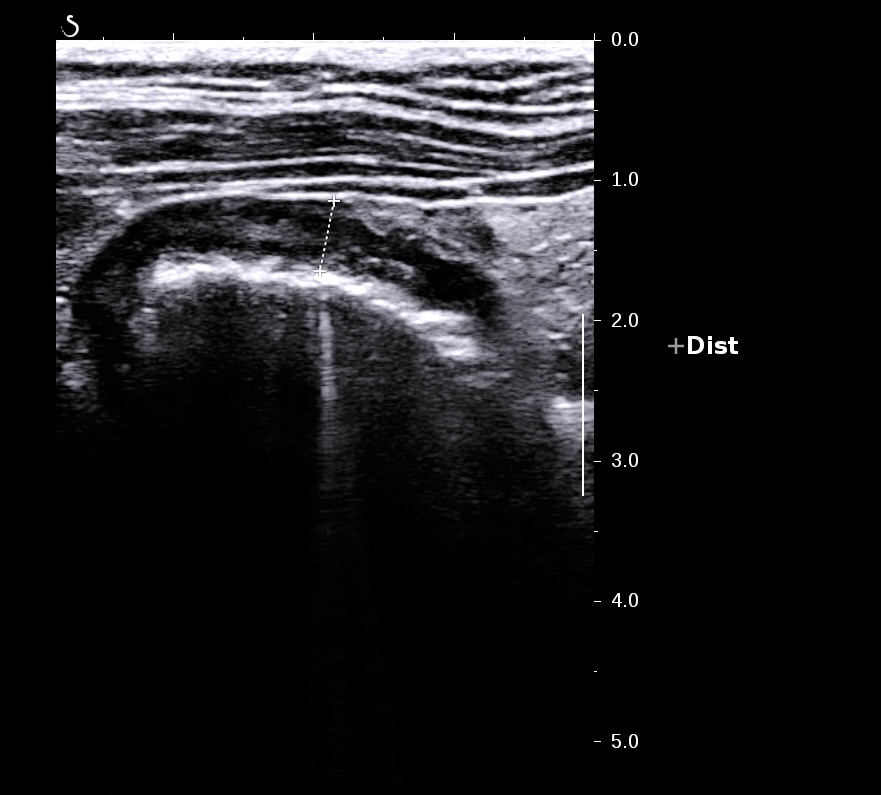

RCH classique, respect de la structure en couche,sous muqueuse très épaissie; musculeuse intacte

Classiquement dans la RCH, l'épaississement concerne les couches 2 et 3, c'est à dire muqueuse (hypoéchogène) et sous muqueuse (hyperéchogène) car il s'agit d'une maladie superficielle de la paroi, la musculeuse (4 ième couche hypoéchogène) est intacte et donc le bord externe est linéaire et régulier

L'épaississement prédomine à la 3 ième couche hyperéchogène (qui fait > 1/3 de la paroi)

Perte des haustrations (le bord externe du colon est rectiligne, lors de la cicatrisation on retrouve des haustrations)